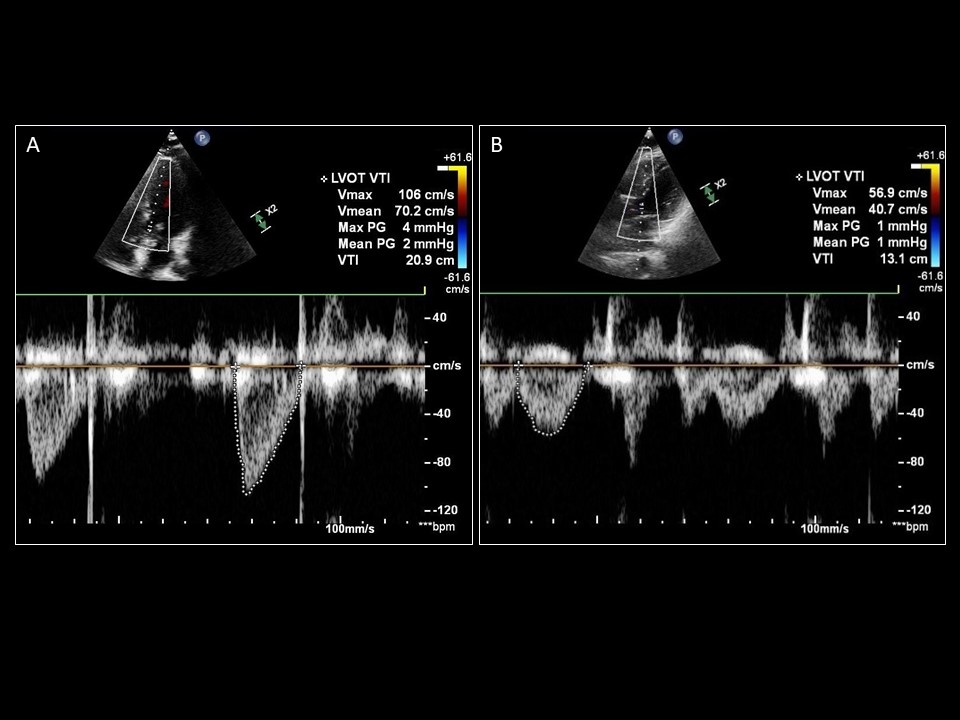

Difference between an LVOT VTI obtained from an (A) appropriate sample location in LVOT with aortic valve closure captured at the end of systole, and (B) a location too proximal in the LV cavity

Sattin, Burhani, Jaidka, Arntfield. How I Do It: Echocardiographic-based Stroke Volume and Cardiac Output Determination. CHEST.